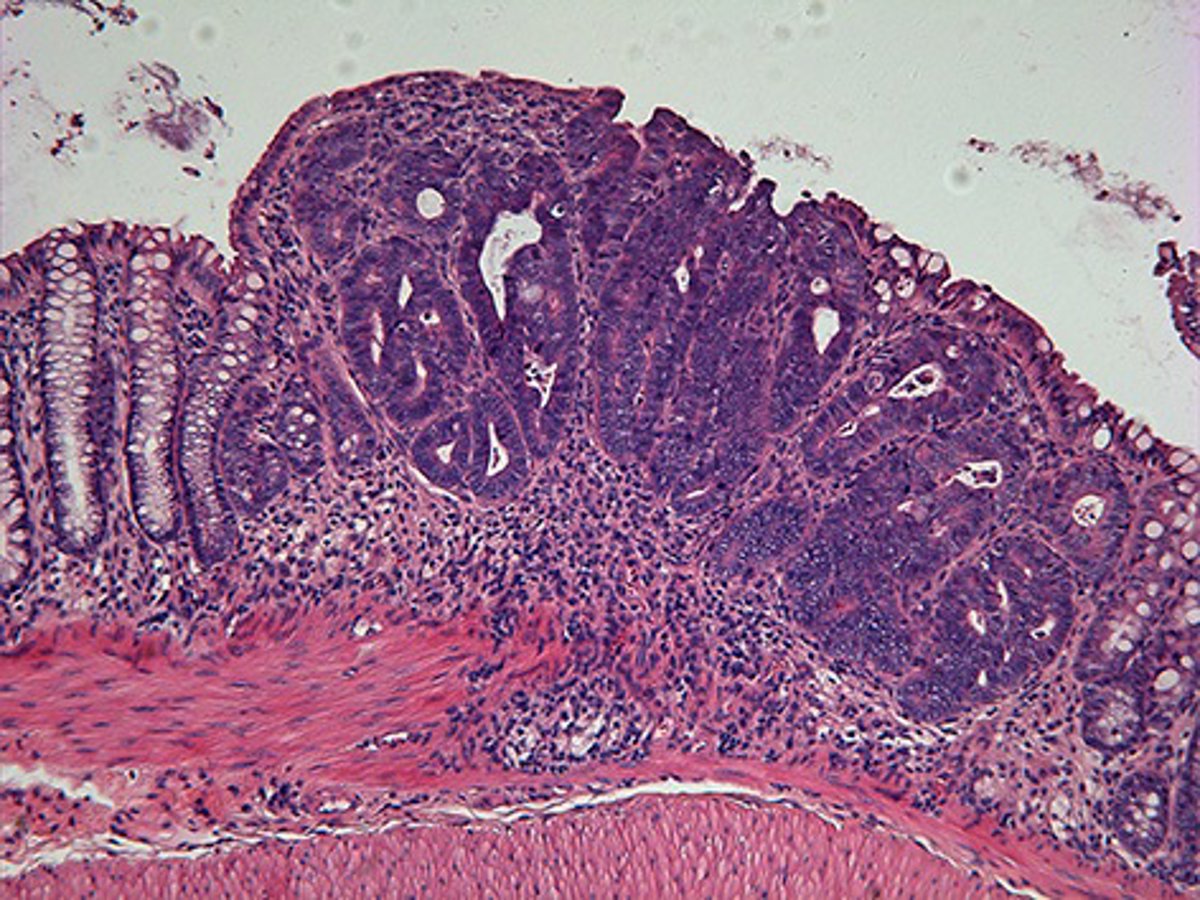

Tumor de colon. Cáncer.

Tumor de colon. Cáncer. - IRB - Archivo

La localización tumoral que aporta un mayor número de casos en Canarias es la de colon y recto (1.656 casos), seguida por los tumores de próstata (1.482), mama (1.397) y pulmón (1.339).